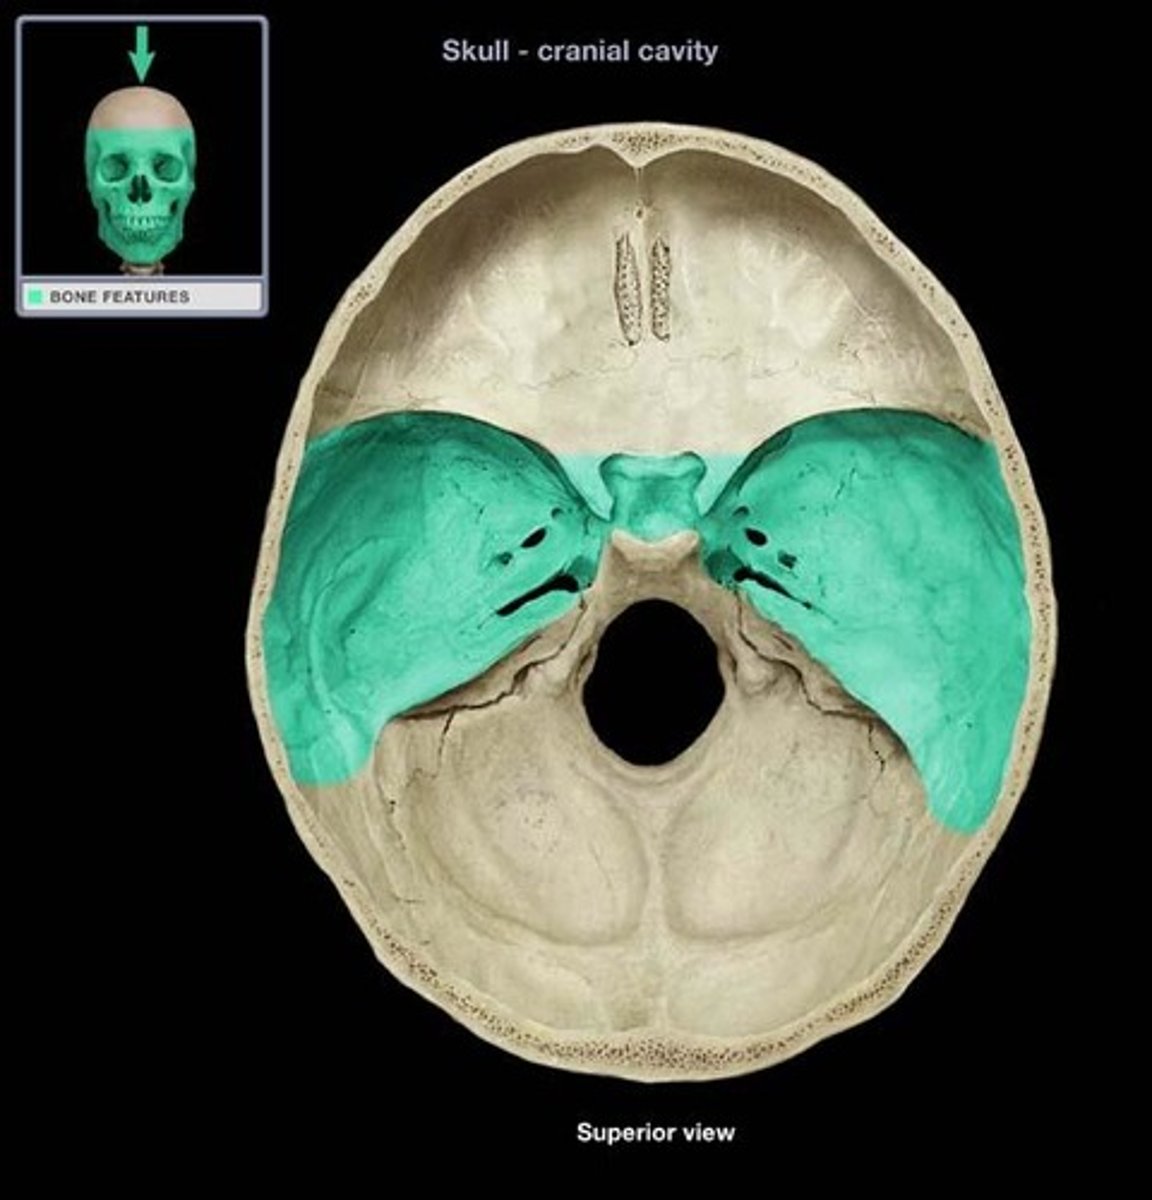

middle cranial fossa

part of the cranial fossa that is the major passageway for cranial nerves 2-6, and houses the temporal lobes & pituitary gland

1. sphenoid (body/greater/lesser wings)

2. temporal bone (squamous & petrous)

what 2 bones make up the middle cranial fossa?